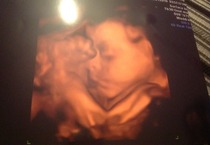

This is my bump at 29+1.

Also a couple photos from our scan yesterday, baby didn't really play ball for longer than a minute but we got a few shots, also saw them open them mouth and yawn was nice.

Lovely pictures scared.

You're sounding more upbeat, scared. Well done on keeping it together overnight. Love your bump pic & scan pics!